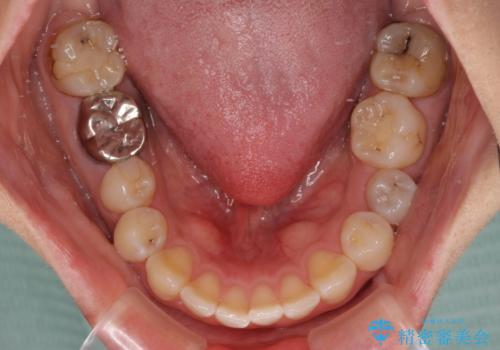

通常は上下左右の第一小臼歯4本を抜歯することになりますが、左側下顎の第二小臼歯は既に根管治療をされており、予後が良くないとのことでこの歯を抜歯し、ワイヤー装置にて矯正治療を行うこととしました。

第二小臼歯抜歯はイレギュラーな治療手段であり、治療期間が延びる傾向にありますが、予定よりも早い2年間で終えることができました。